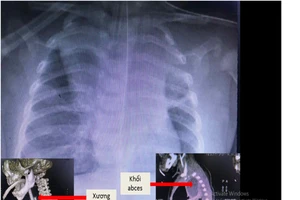

Bé trai 5 tuổi ho khò khè suốt 2 tháng vì lý do không ngờ

Bé trai nguy kịch vì mảnh xương lươn cắm chặt thực quản 5 ngày